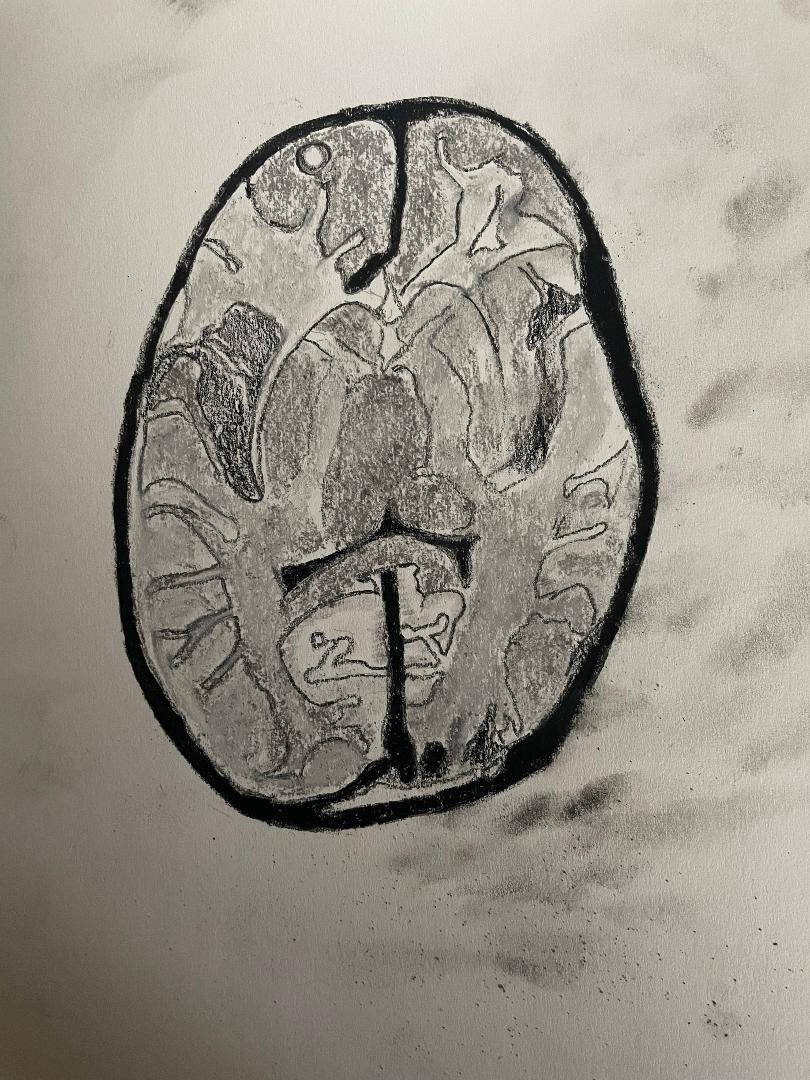

Mesial Temporal Sclerosis